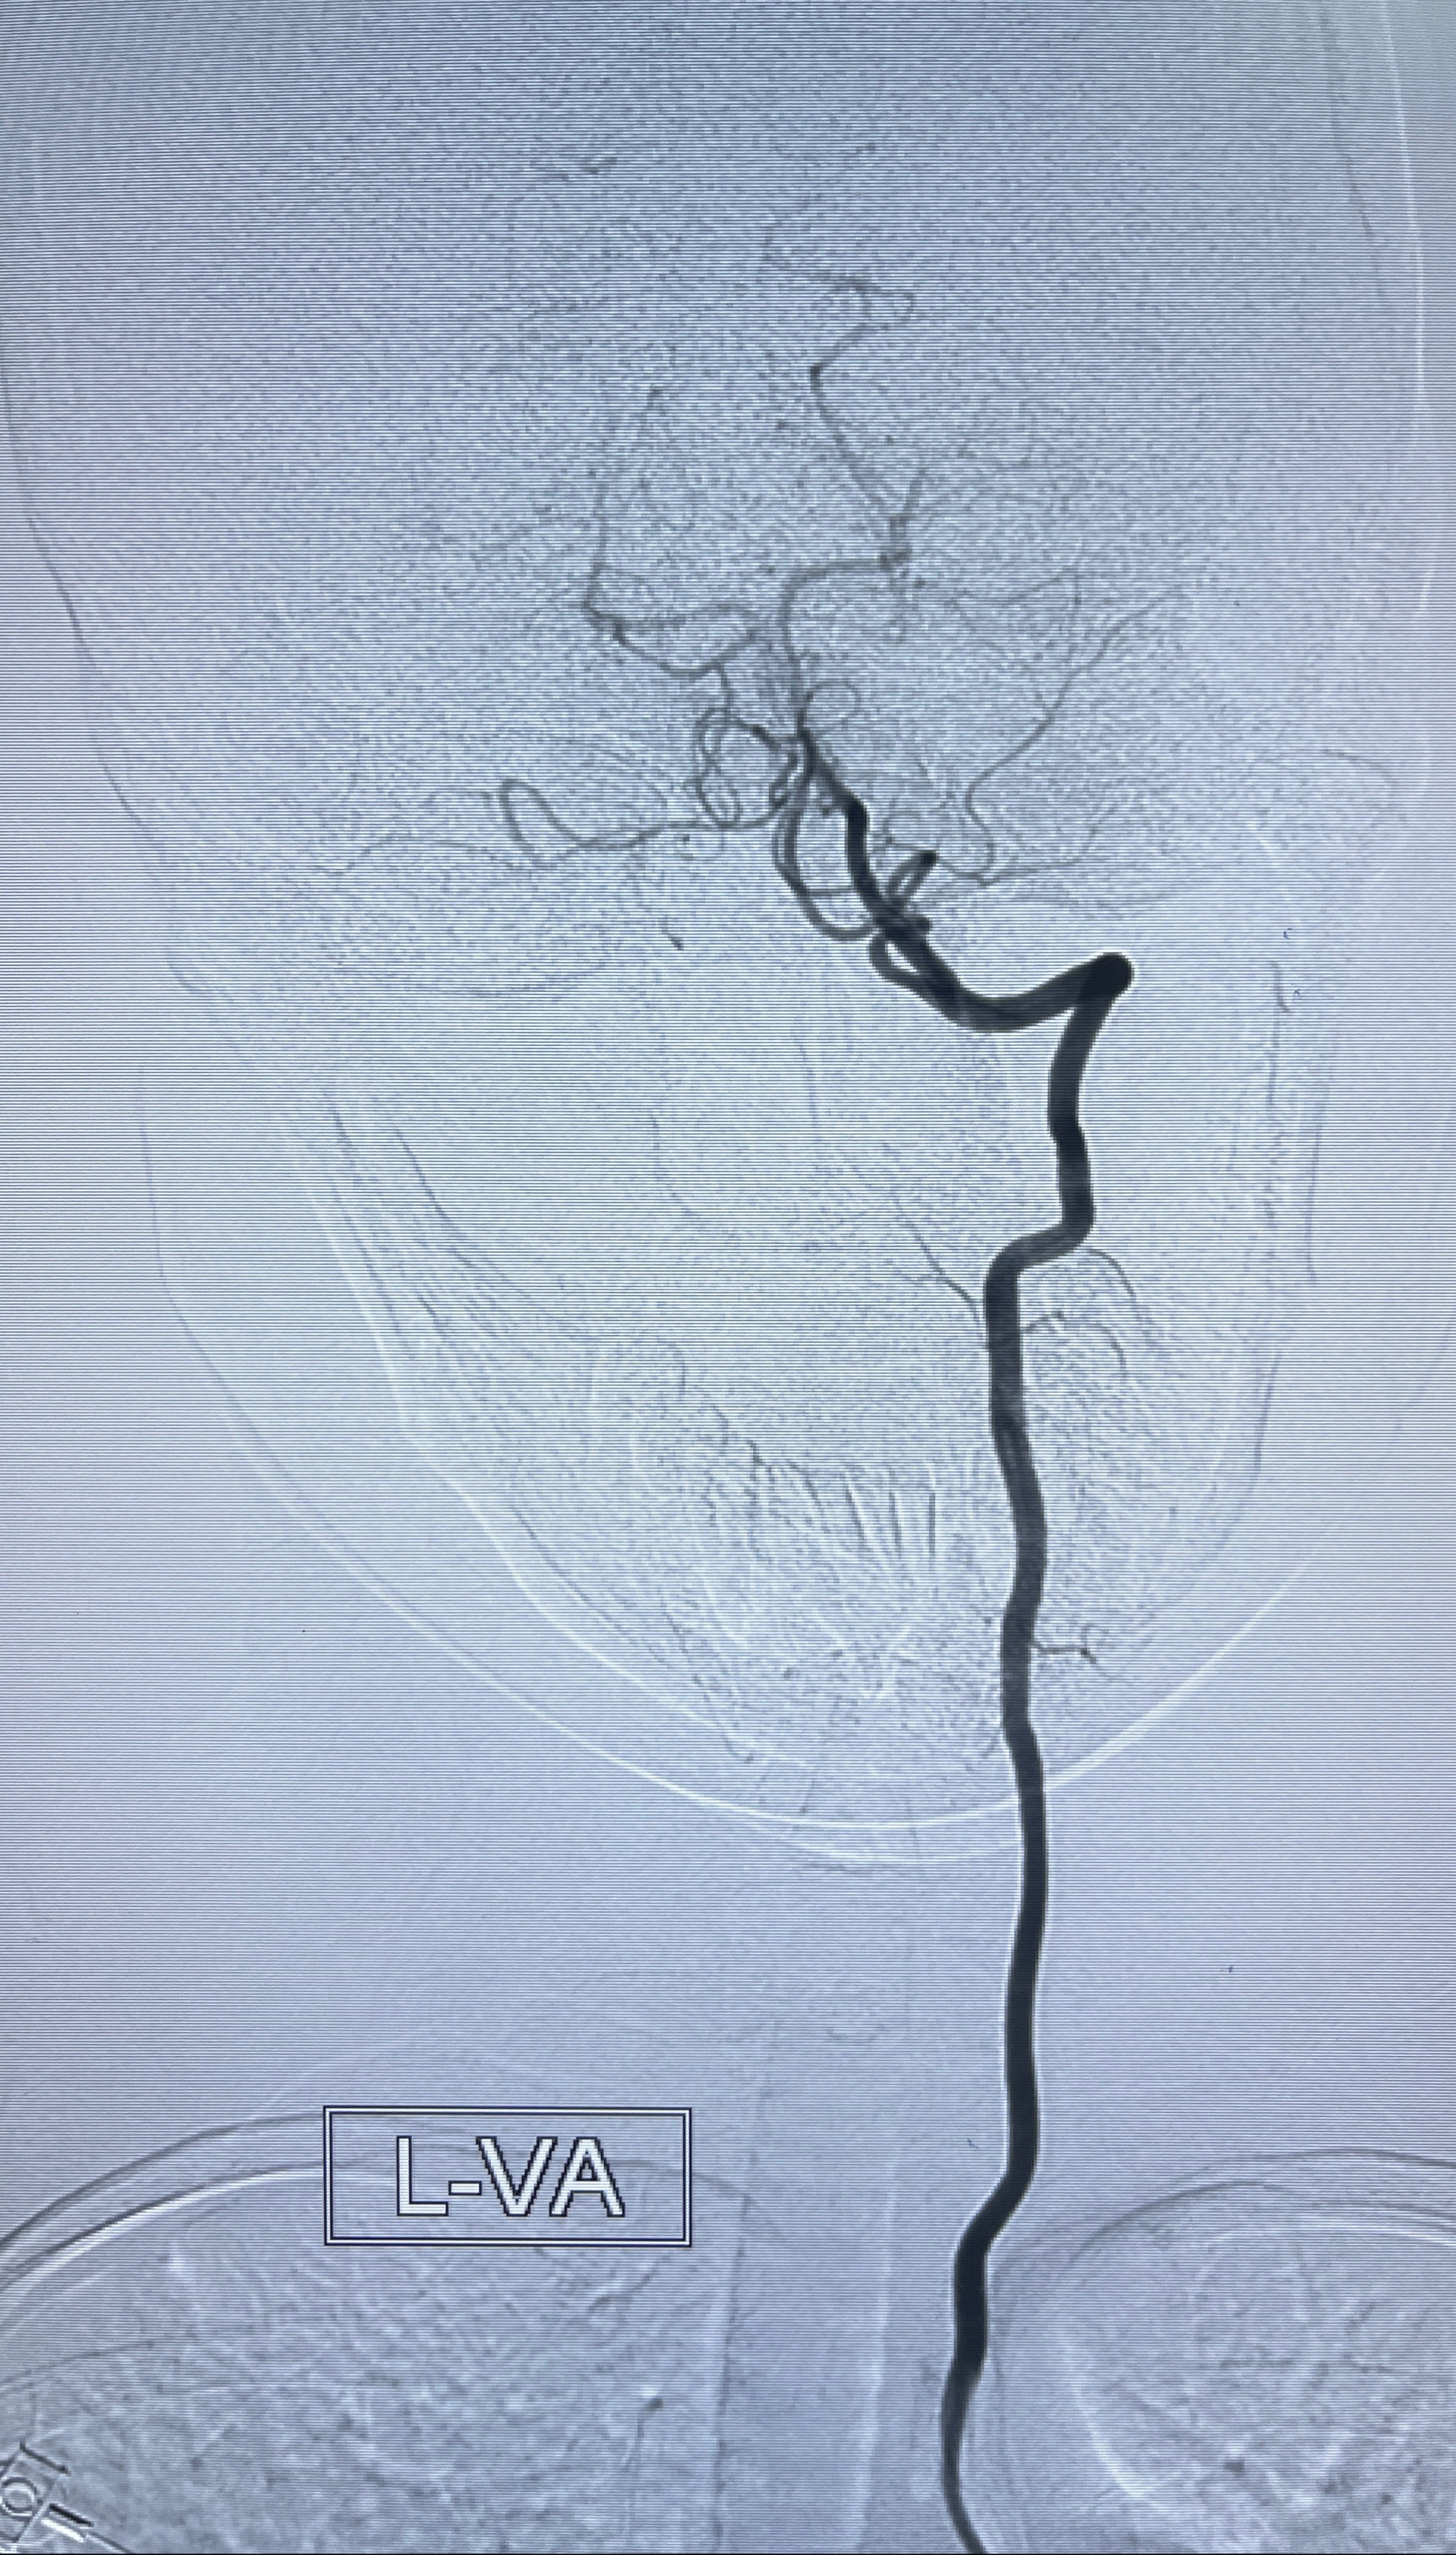

现病史:患者2023-07-12体检时头颅MRI提示:左侧大脑中动脉可疑病灶,遂于上海大学附属第三医院查头颅CTA提示:左侧大脑中动脉M1段动脉瘤,右侧大脑前动脉A1段缺如,左侧椎动脉V4段纤细。追问既往病史,患者诉十余年来睡眠不佳,反复头痛,偶有视物模糊,服用佐匹克隆、维生素B1、谷维素、刺五加片治疗,睡眠有改善。现患者有头痛不适,为求进一步诊疗左侧大脑中动脉M1段动脉瘤至我科就诊,收治入院。

辅助检查:2023-07-12 上海大学附属第三医院 头颅CTA:左侧大脑中动脉M1段动脉瘤(1.7*3.4mm),右侧大脑前动脉A1段缺如,左侧椎动脉V4段纤细。

2023-08-14DSA:

左侧大脑中动脉动脉瘤,约2.6-2.8-3.4-2mm大小(瘤颈部、瘤体部、瘤高)